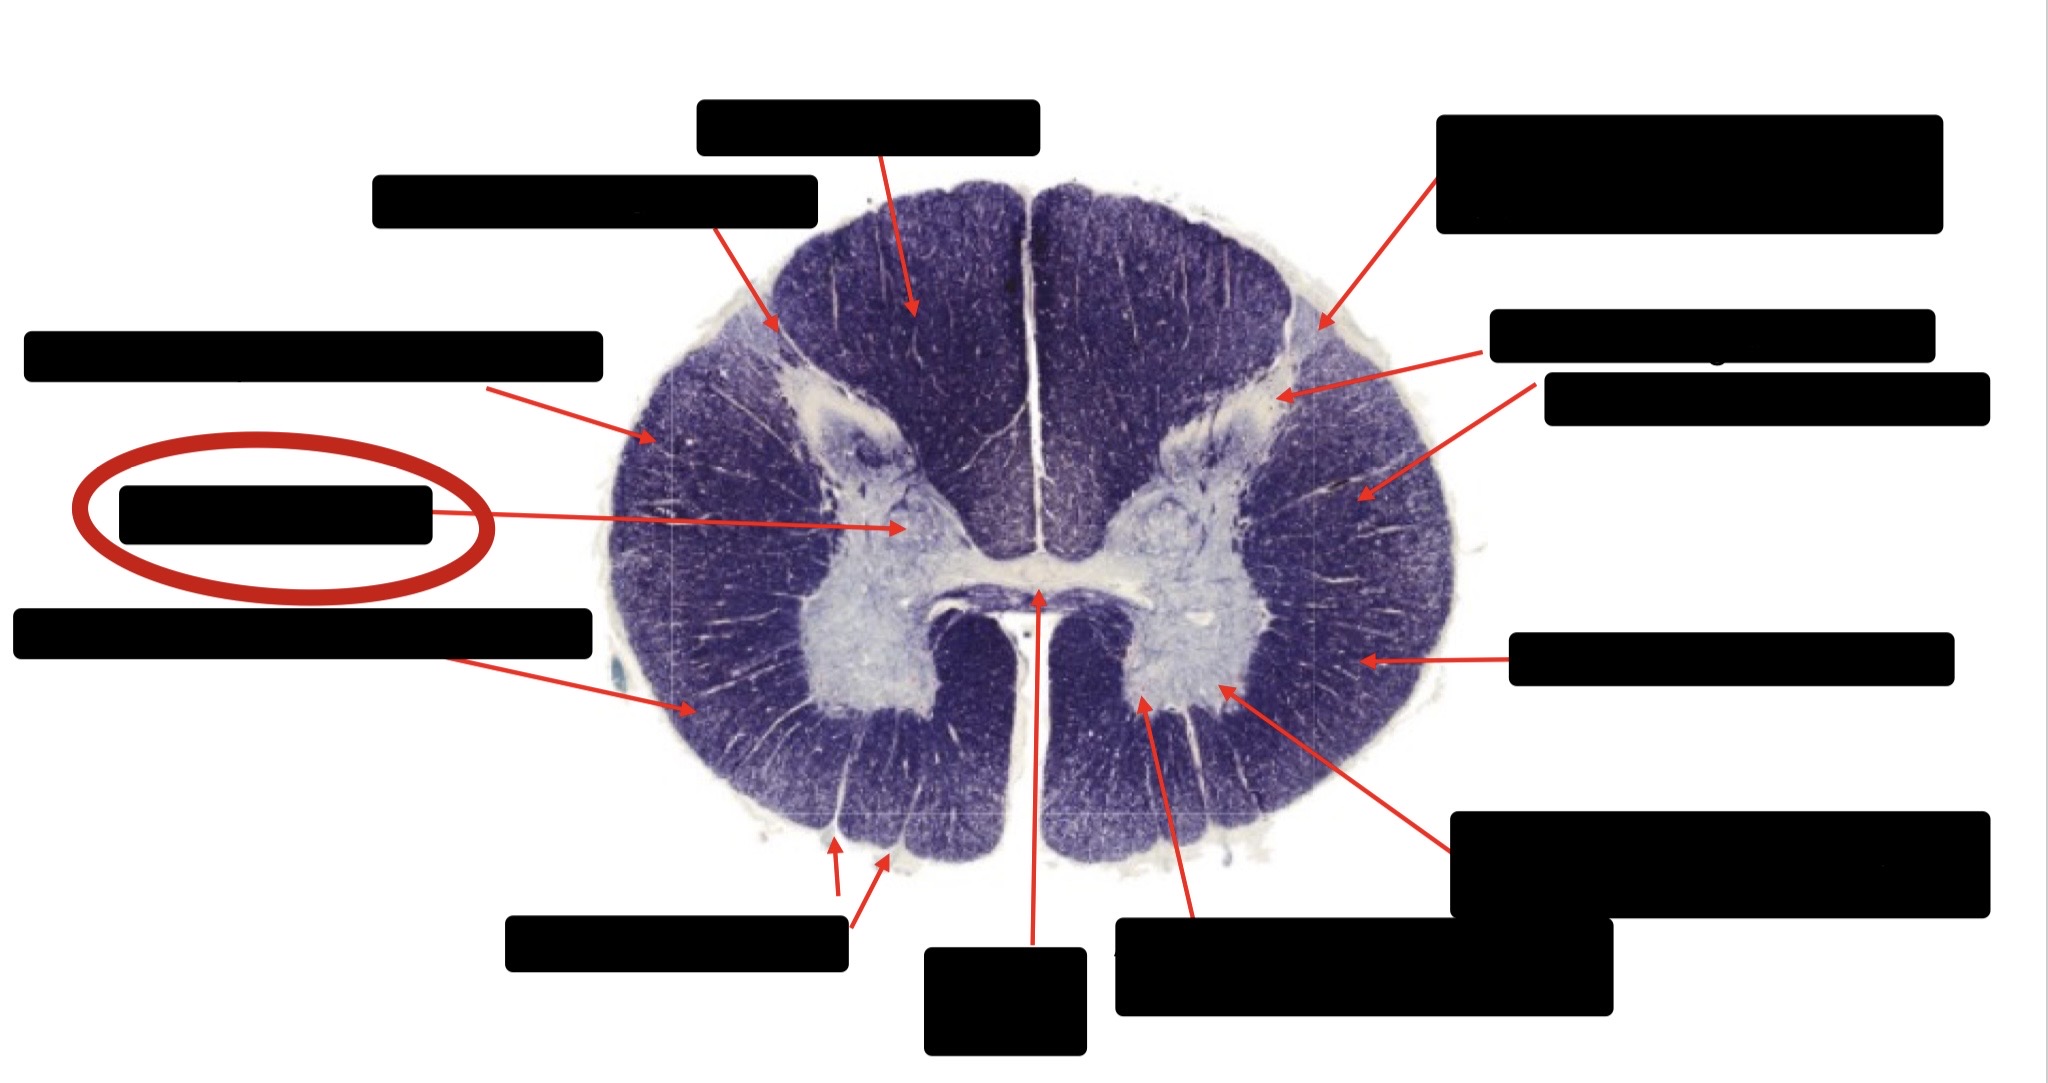

Posterior Column (Fasciculus Gracilis)

Large Fiber Entry Zone

Lissaeur’s Tract & Small Fiber Entry Zone

Substantia Gelatinosa

Lateral Corticospinal Tract

Ventral Root Fibers

Anterior Horn Motor Neurons

Anterior Medial Fissure

Dorsal Rootlet

Posterior Spinocerebellar Tract

Anterior Spinocerebellar Tract

Spinothalmic Tract

Posterior Column (Fasciculus Cuneatus)

Anterior Horn Motor Neurons (Distal Muscles)

Anterior Horn Motor Neurons (Proximal Muscles)

Central Canal

Anterior Corticospinal Tract